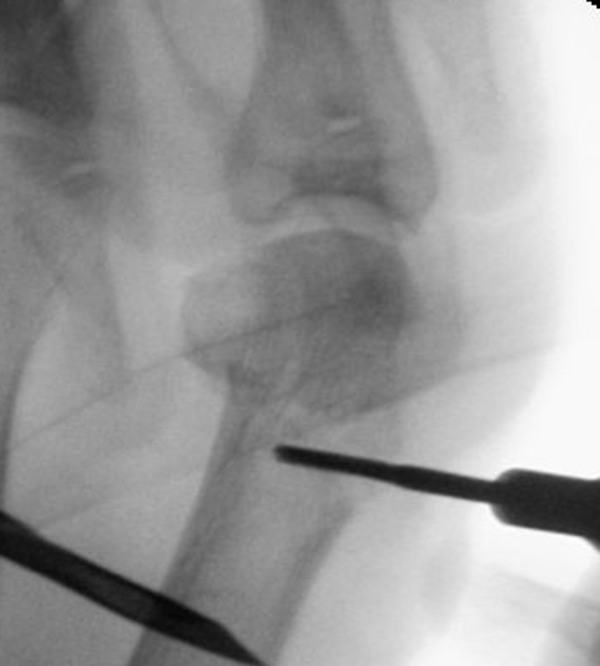

• Positionierung des Bildwandlers: 90° Winkel zum Os metatarsale I. Benötigt wird die Durchleuchtung des Vorfußes a.p., seitlich und schräg.

Operationstechnik

Der von Isham/Reverdin beschriebenen minimal invasiven Technik zur Korrektur einer Hallux valgus Deformität liegen 4 Operationsschritte zu Grunde:

2. Subcapitale intraartikuläre Osteotomie

Die Folge der Operationsschritte sollte strikt von 1. - 4. erfolgen, da ansonsten die mediale Closing Wedge Osteotomie bei vorzeitigem lateralem Release und/oder Akin Osteotomie nicht geschlossen werden kann. Nach der von Isham beschriebenen Originaltechnik finden Implantate keine Anwendung, zur Sicherung und besseren Fixation können osteosynthetische Verfahren angewandt werden (siehe auch Fehler, Gefahren und Komplikationen).